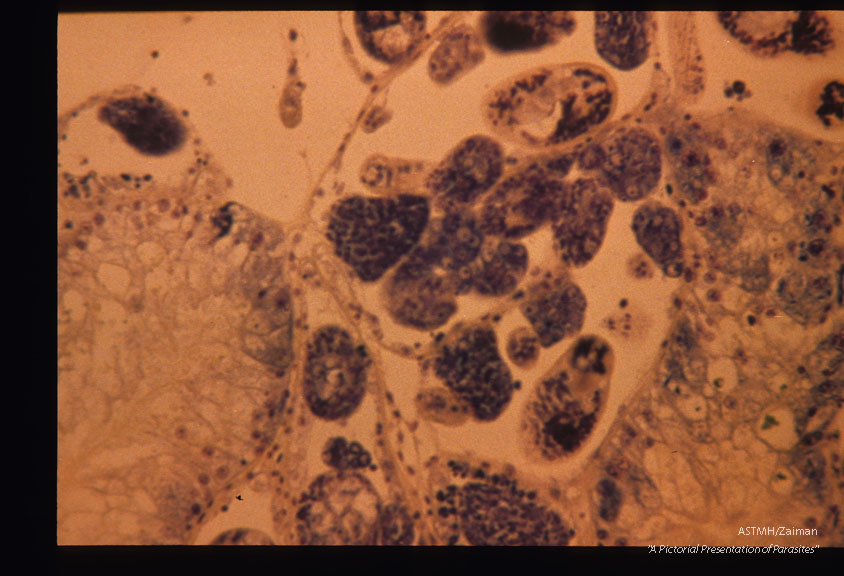

Sections through snail (Biomphalaria glabrata) liver containing sporocysts 54 days after infection.

Schistosoma mansoni

Description: Sections through snail (Biomphalaria glabrata) liver containing sporocysts 54 days after infection.